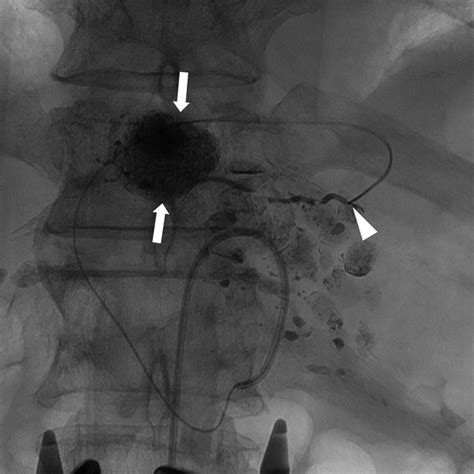

In the modern medical landscape, the Inferior Phrenic Artery has gained immense importance, particularly regarding Hepatocellular Carcinoma (HCC). When treating liver tumors that are supplied by the hepatic artery, interventional radiologists often encounter situations where the tumor has recruited extrahepatic collateral blood supply.

The right IPA is the most common collateral source for these tumors when the hepatic artery supply is compromised or insufficient. During Transarterial Chemoembolization (TACE), identifying and catheterizing the IPA is often necessary to ensure that the tumor receives the full intended dose of therapeutic agents.

• Vascular Variability: Operators must be cautious of the connection between the IPA and the hepatic arteries, as accidental embolization of the wrong vessel can lead to significant organ damage.

• Catheterization Techniques: Utilizing microcatheters is essential to navigate the often tortuous path of the IPA to prevent vasospasm.